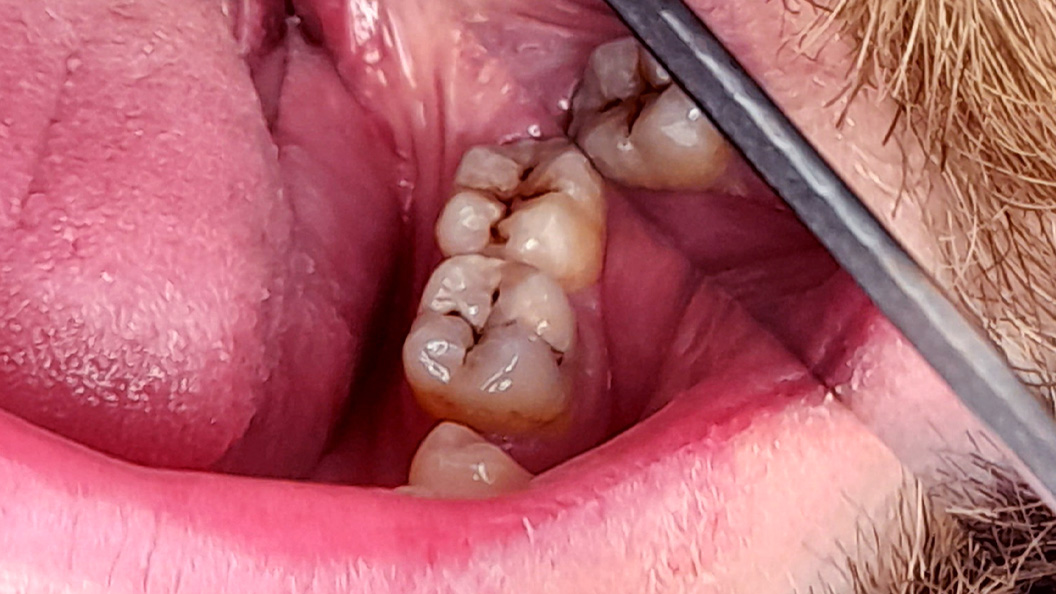

До и после лечения

В «Стоматологию Комфорта» обратился пациент с жалобами на наличие кариозных полостей и кратковременную боль от холодного в области 37 и 38 зубов. Терапевт Похилько Надежда Геннадьевна в ходе осмотра выявила кариозные поражения на окклюзионной и вестибулярной поверхностях 37 зуба, а также на окклюзионной и мезиальной поверхностях 38 зуба. Зондирование было болезненным. После препарирования полостей под контролем кариес-маркера, врачом был поставлен диагноз: глубокий кариес 37 и 38 зуба. Было принято решение о лечении с дальнейшей постановкой пломб из композита светового отверждения Estelite.